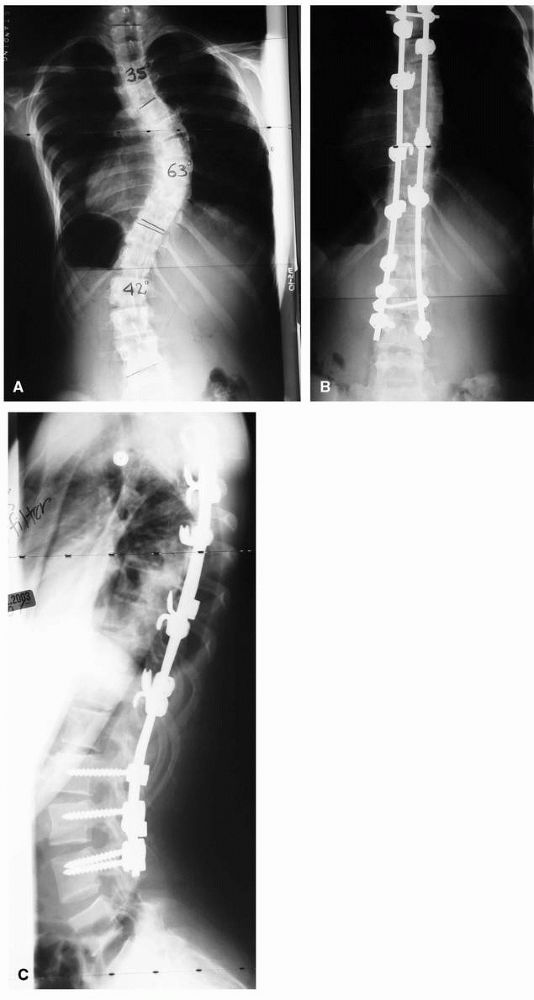

![]() |

FIGURE 16-15. Spinal fusion for progressive idiopathic scoliosis using a hybrid system of rods, hooks, and pedicle screws. (A) preoperative PA view; (B) postoperative PA; and (C) lateral view.

|